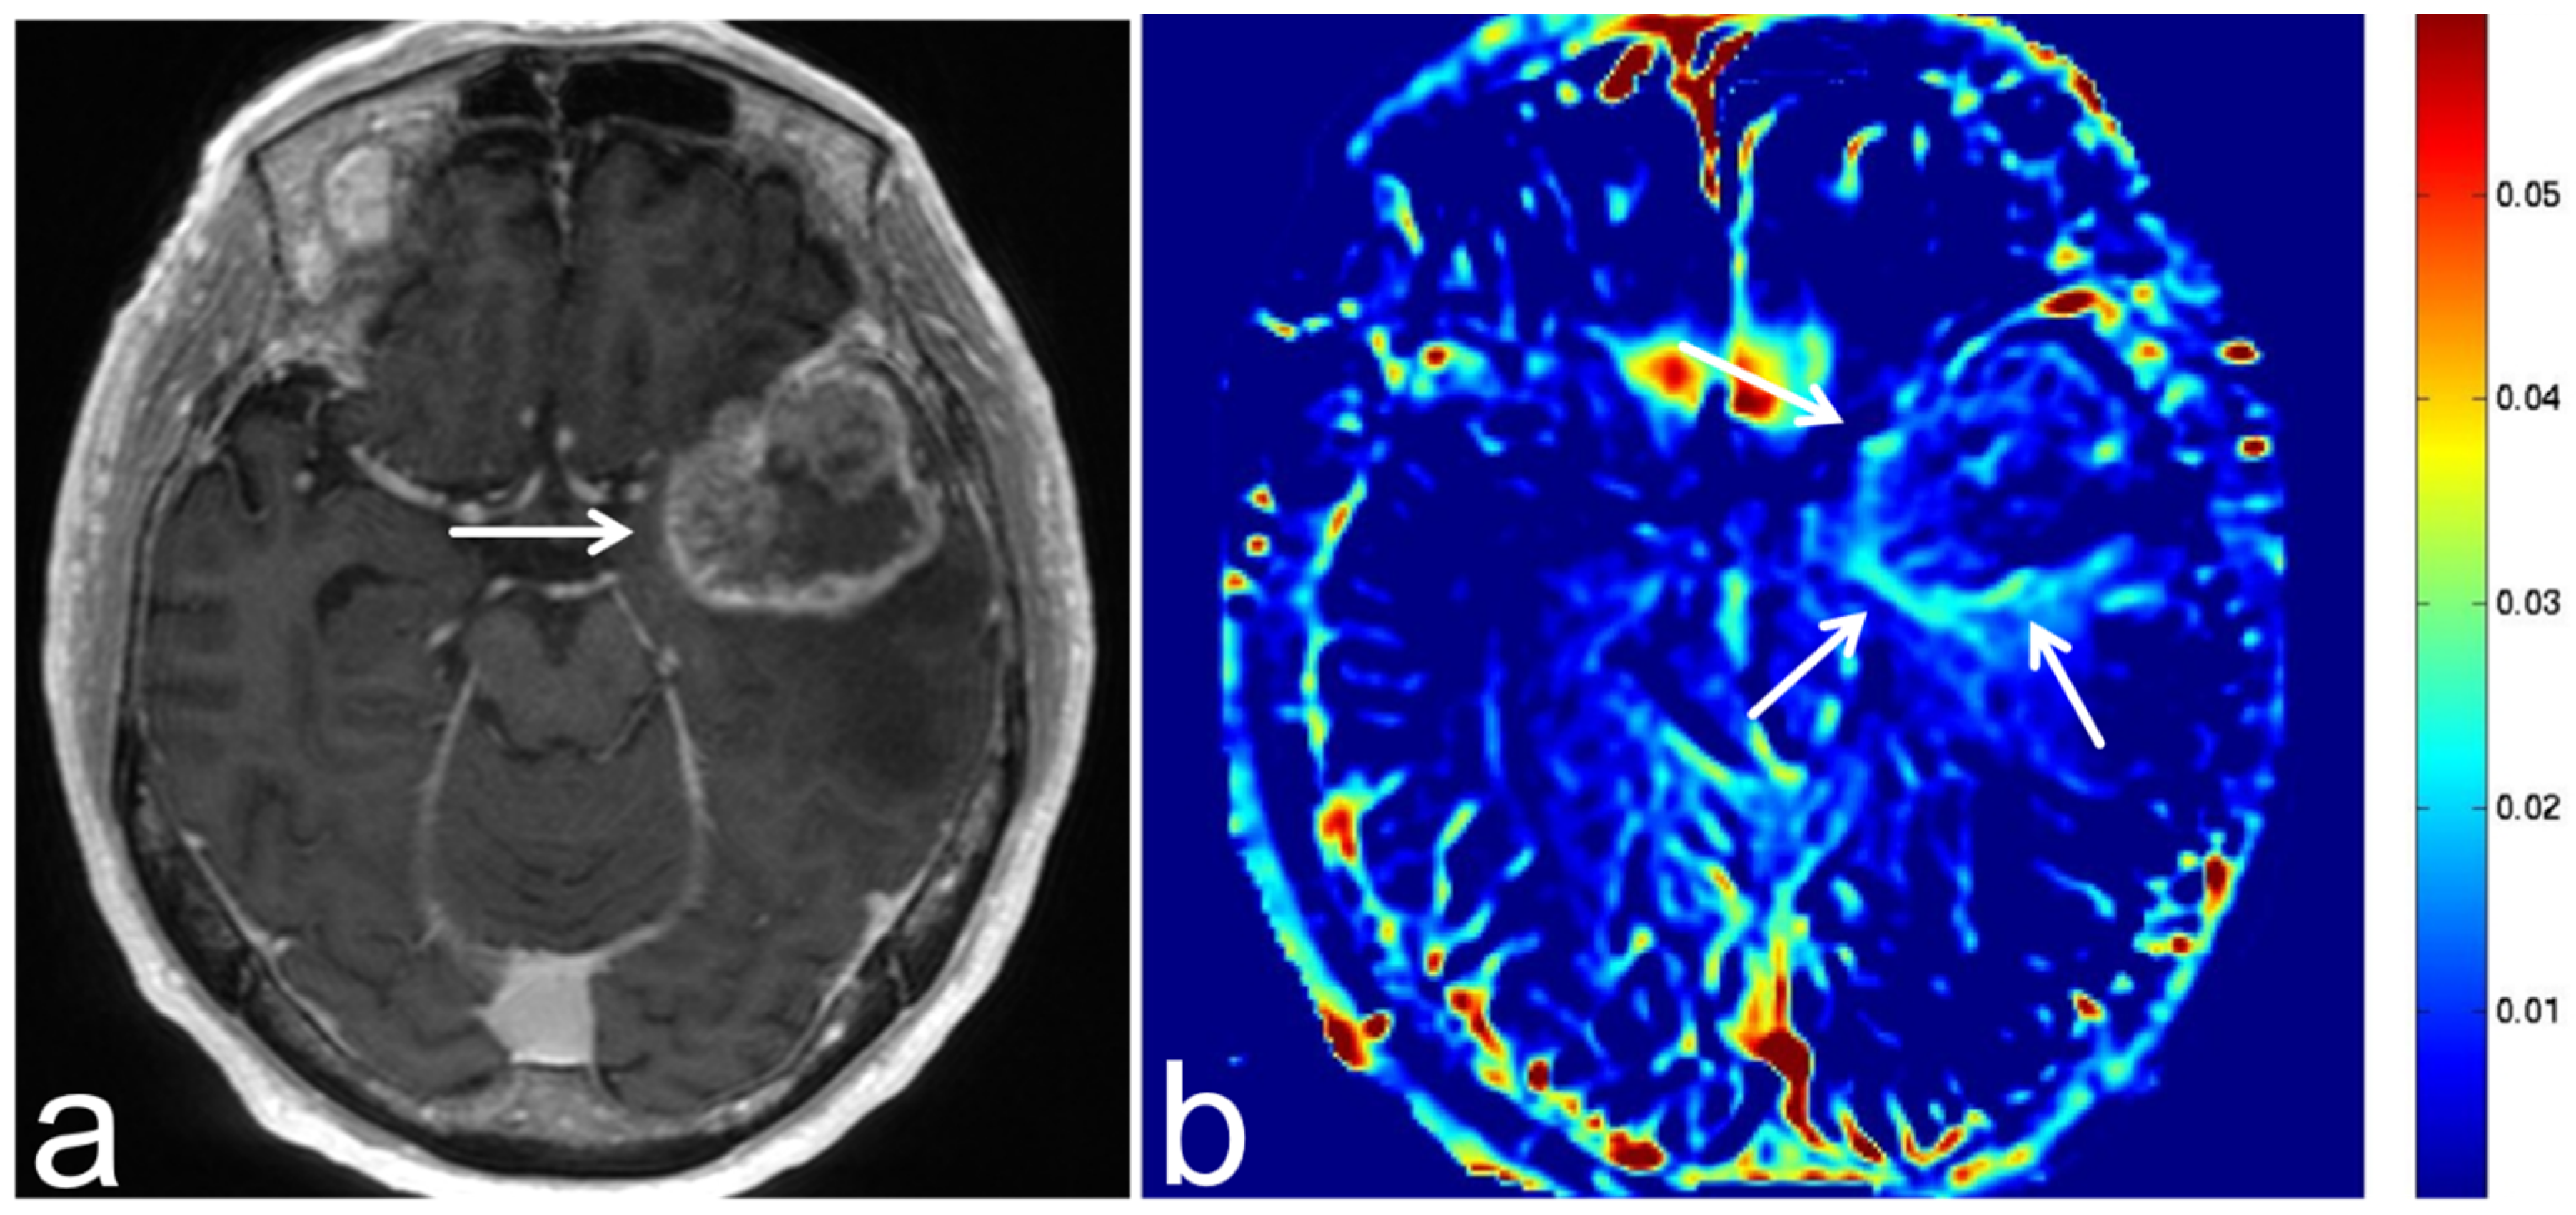

5.4. Malignant Lymphoma

5.5. Brain Metastasis